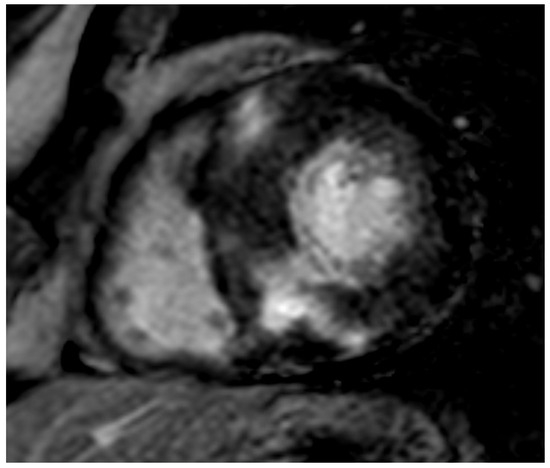

Figure 3.

ATTR elderly patient. Transmural semicircumferential LGE pattern and symmetric thickening of the left ventricle with septum maximally measuring 21 mm.